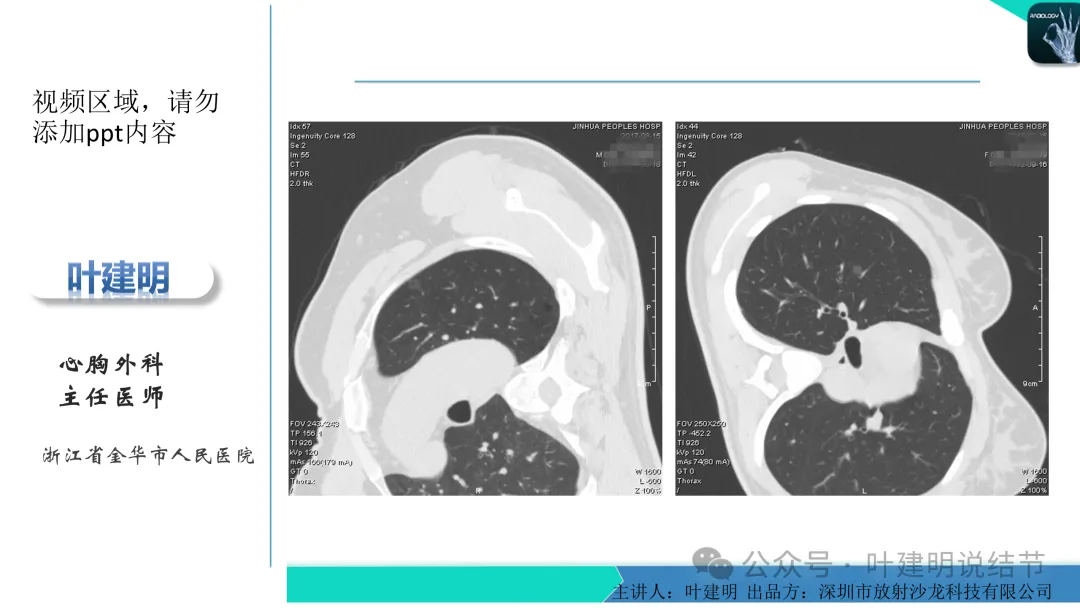

当地说考虑微浸润性腺癌的左下主病灶影像连续层面展示:

病灶出现,显模糊。

上图层面轮廓较清,但密度很淡,似见血管走行,但靠左前方的似条状磨玻璃密度与血管连着的到底是血管分支还是结节的一部分,其实并不确切。如果其实是血管分支,那病灶与它之间就不是空泡。

病灶在此层整体边缘显糊,灶内有空泡似的,瘤肺边界欠清。

边缘不平,还是灶内多发小空泡?邻近血管与之紧贴,但血管无异常走行。病灶密度很低,显糊。

中间所谓空泡更像是细支气管扩张,内壁非常光滑且圆形。

病灶边缘区淡而模糊。

这个病灶会是微浸润性腺癌吗?当然没有病理诊断,我也不能说百分之百必不会,但这样的病灶已经风险大到必得尽快手术切除干预了吗?显然还早着呢:1、影像不是典型的结节状;2、边缘与轮廓模糊不清;3、灶内似有细支气管扩张(更容易是细支气管扩张伴少许周围炎或肺泡上皮增生);4、血管邻近走但无牵拉影响;5、没有实性成分,没有锐利毛刺,没有胸膜牵拉,没有血管进入,没有任何倾向风险性高的影像特点。我一直强调:肺结节是否要干预处理,不要纠结于最后病理是什么,而要看风险高低;而风险高低的最重要术前判断依据一是随访有无进展,二是有没有实性成分。只要没有肉眼可见的影像上的实性成分,风险就是低的!何况病理也是人看的,原位还是微浸润,不典型增生还是原位有时也在一念之间。